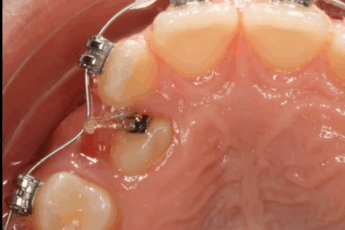

Absceso dental: una infección que causa dolor e inflamación alrededor de un diente.

Las úlceras o abrasiones pueden ser causadas por traumas como alimentos duros o cepillado incorrecto.